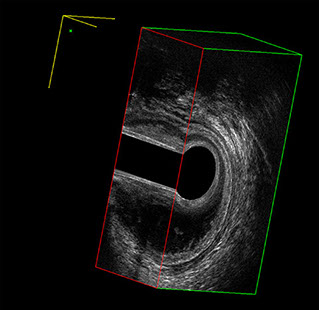

Sezione Longitudinale 3D con Tramite Fistoloso Intersfinterico Basso Anteriore Semplice

L’ecografia transanale è un esame diagnostico per immagini che consiste nell’introduzione di un trasduttore ad ultrasuoni. Le immagini qualitativamente migliori del canale anale sono ottenute usando un trasduttore rotante, montato in un manipolo rigido, che fornisce un’immagine a 360°. Con le apparecchiature più moderne è anche possibile ottenere immagini tridimensionali.

L’ecografia transanale permette di distinguere la sottomucosa che riveste il canale anale, lo sfintere anale interno, e lo sfintere anale esterno.

Proctal dispone di apparecchiatura per ecografia endoanale 3D con sonda rotante.